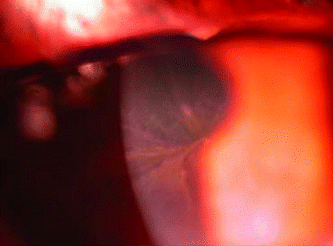

Figure 2. A photograph that illustrates the fit of a GPlens. |

What's better than written notes or drawings? What says a thousand words in an instant? It's the photograph. With one quick look, you can tell that the eye in Figure 1 has an ocular surface problem, or what kind of fit a GP lens has in Figure 2.

7. This image of an amiadurone swirl was taken |

On a slit lamp, the illumination is more complicated. The brighter the light, the faster the shutter speed, which means that camera movement is minimized. But if there's too much light, corneal reflections and patient discomfort are more likely to occur. Use too little light and the picture becomes fuzzy because of camera shake or patient eye movements. A good picture deserves a balance of all of these factors.